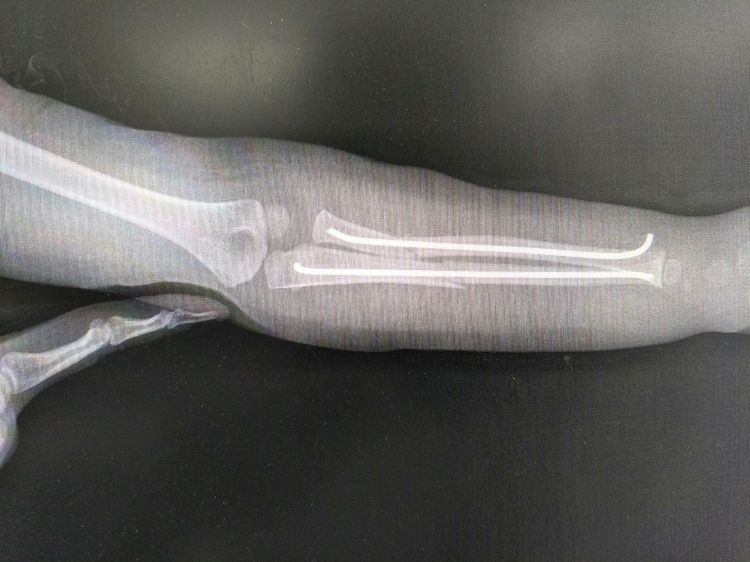

术后一个月拍片复查,内固定克氏针位置良好,骨折端对位对线好,骨折端骨痂生长。

由于小孩子天性活泼好动容易摔伤,加之近年来日益复杂的交通环境导致车祸增多,致使儿童骨折的发生率呈上升趋势,应用克氏针模拟弹性髓内针技术治疗小儿四肢干性骨折,不需要切开骨折端,剥离骨膜,不破坏骨折端血运,最重要的是不干扰骨骺生长,克氏针固定后骨折端存在微动,更有利于骨折端骨痂形成与骨折愈合,手术切口小,创伤小,骨折愈合快,住院时间短,术后并发症低,术后3周即可进行功能锻炼,术后1个月基本恢复正常,不影响患儿生长发育。小儿骨科目前在通辽地区还是短板,目前,通辽市医院骨二科在张继锋主任、肖海祥副主任医师带领下,逐步开展小儿骨折微创手术,对于小儿肱骨近端骨折、肱骨髁上骨折、前臂双骨折及小儿下肢骨折的微创治疗积累了丰富的临床经验,我们将继续努力,克服短板,把短板变成专长,精益求精,为患者提供最高质量的微创手术。